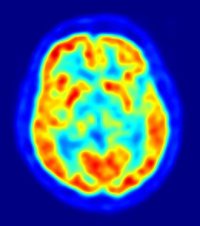

Los niños con autismo regresivo tienen cerebros más grandes

Cerebro humano

En el mayor estudio sobre el desarrollo del cerebro en niños preescolares con autismo hasta la fecha, una investigación realizada por investigadores de la Universidad de California en Davis, ha observado que los niños de 3 años de edad con autismo regresivo, y no con autismo de inicio temprano, tienen cerebros más grandes que sus contrapartes sanas. El estudio ha sido publicado en 'Proceedings of the National Academy of Sciences' (PNAS).

Los investigadores recogieron imágenes por resonancia magnética (IRM) de 180 participantes de 3 años de edad. Para evaluar la tasa de crecimiento del cerebro antes de los 3 años, los investigadores analizaron las mediciones de circunferencia de la cabeza del niño sano realizadas en las visitas al pediatra desde su nacimiento hasta los 18 meses.

Las imágenes de resonancia magnética se llevaron a cabo en los participantes del estudio durante el sueño natural, utilizando protocolos desarrollados específicamente para el Proyecto de Autismo Fenoma.

Según el estudio, el crecimiento de la cabeza y la ampliación acelerada del cerebro se observó consistentemente sólo en el subgrupo de niños con diagnóstico de autismo regresivo; en concreto, el volumen cerebral total a los tres años de edad en los varones con autismo regresivo era un 6 por ciento mayor que el de los niños con un desarrollo típico.